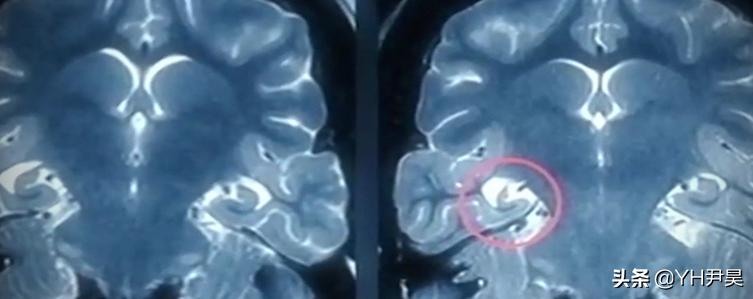

与此同时另一组解刨小队也得出了相同的结论,海狮解刨队一共解刨了30只因病去世的海狮并将这些海狮身体里器官挨个拿出来检查,结果发现这些海狮心脏里面没斑点,肾脏里面没结石,肝脏里面没硬块,肠胃里面没穿孔,所有的内脏器官都非常健康没有任何问题,不过当调查人员对海狮大脑进行检测时发现,这些海狮大脑内的海马回都出现了损害,海马回又叫海马体他位于海狮大脑中的最深处主要负责长时 记忆 的存储转换和定向等功能,如果海马回出现问题就会出现痉挛,无法辨别方向,失忆等症状,

受伤的海狮大脑

与此同时调查员还在这些痉挛海狮的臭臭里检测出了软骨藻酸毒素,这也就表明了这群海狮确实是由于感染了软骨藻酸毒素,导致的大脑中海马回受到损伤从而引发的痉挛,至此痉挛海狮的病因算是彻底查清了但是还有三个谜团没能解开